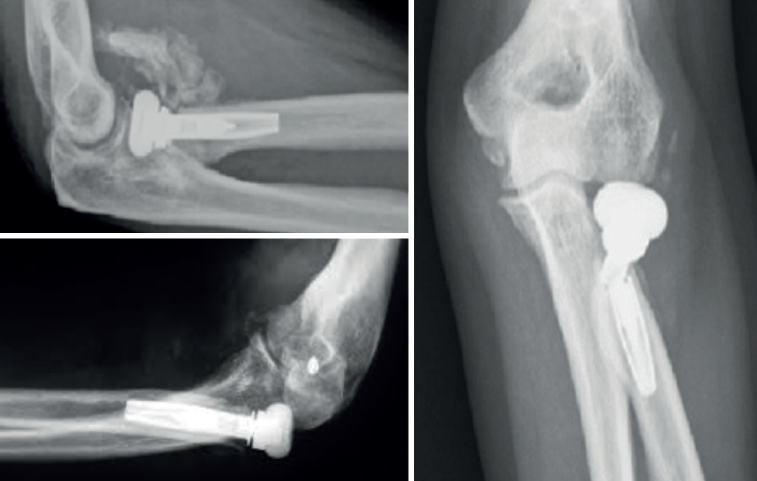

Otras complicaciones que pueden ocurrir son las osificaciones ectópicas, asociadas generalmente a rigidez articular importante. Menos habituales son la luxación del implante y su rotura (Figura 4).